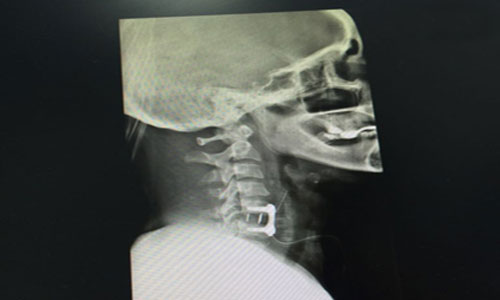

حضرت مريضة سعودية تعاني من كسر وخلع بالفقرات العنقية الخامسة والسادسة وضعف بالأطراف العلوية، وبعد عرض الحالة على الدكتور حازم فريد جراح العمود الفقري حيث قام بإجراء عملية جراحية لإصلاح الخلع وتثبيت الفقرات العنقية بواسطة شريحة ومسامير وبعد الجراحة تماثلت المريضة للشفاء وتحسنت قوة العضلات بفضل الله تعالى وخرجت المريضة بحالة جيدة.